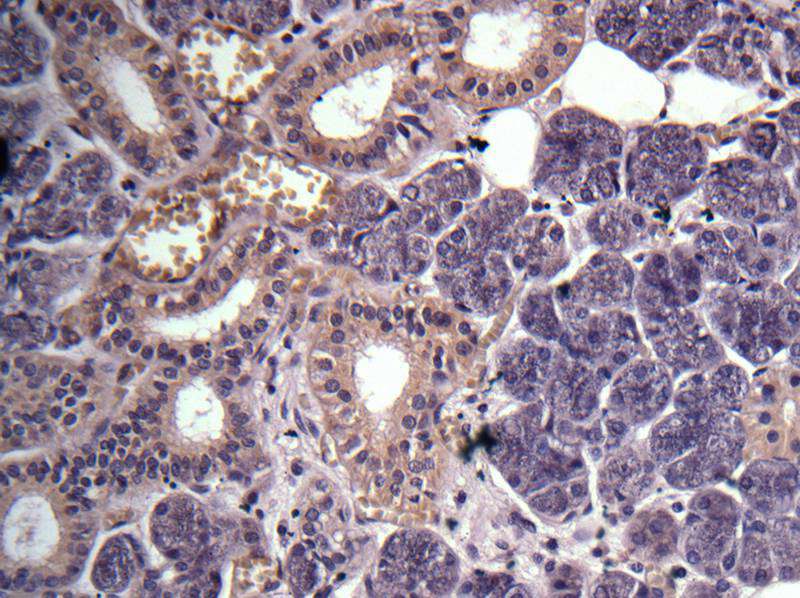

图片:

Immunohistochemical analysis of Salivary gland cancer, using GPR114 antibody at 1: 100 dilution.